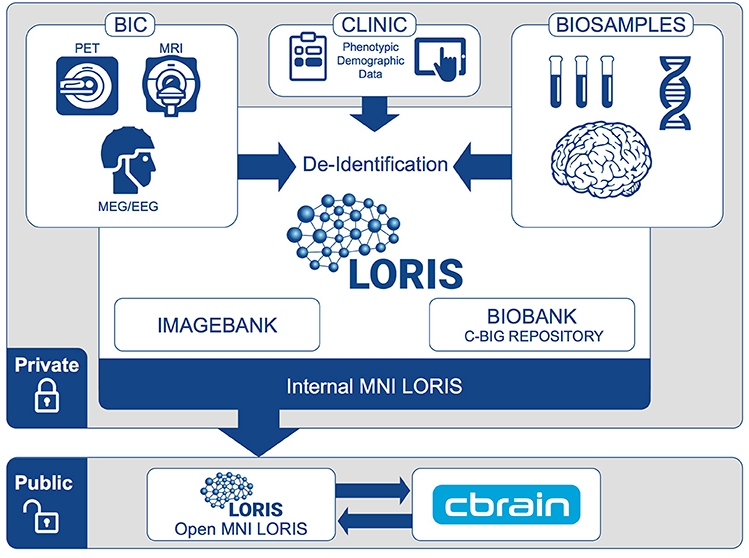

LORIS-CBRAIN INTEGRATION

Heterogenous Data

Imaging Data

1. Acquisition & Storage

- Data Sharing - Cross project collaborations

- Heterogeneous Data Management - Single platform for MRI, PET, Clinical & Genetics data

- Biobanking - Tissue, blood and saliva samples

Data Sharing Initiatives

Public Data Repositories

Collaborative Data releases

CBRAIN hooks

Open Science at the MNI